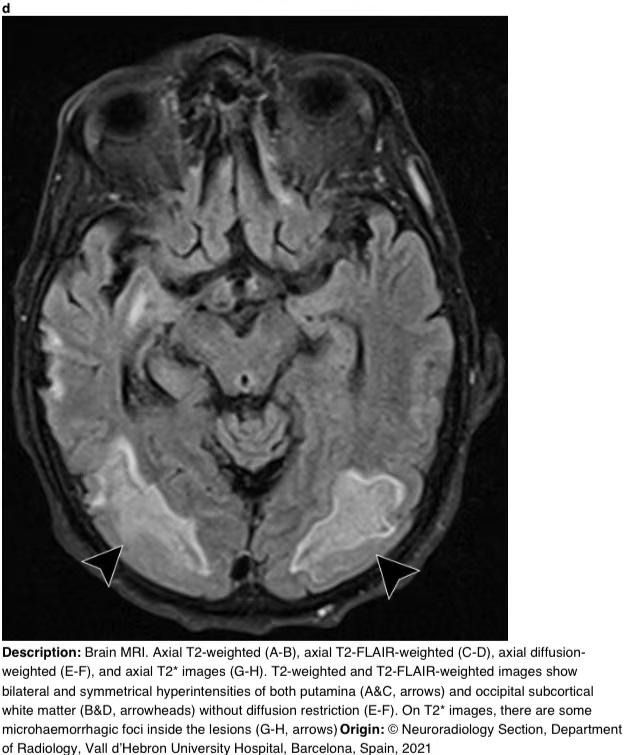

在16天的随访中,脑部MRI显示壳核和枕下皮质下白质上对称的T2/FLAIR高信号。T2图像显示病变内有微出血(图3)。

图3 a-h 脑部核磁共振成像。轴向T2加权(A-B)、轴向T2 FLAIR加权(C-D)、轴向弥散加权(E-F)和轴向T2图像(G-H)。T2加权和T2 FLAIR加权图像显示双侧和对称的壳核高信号(A和C,箭头)和枕下皮质下白质高信号(B和D,箭头),无弥散限制(E-F)。在T2图像上,病变内有一些微出血病灶(G-H,箭头)。